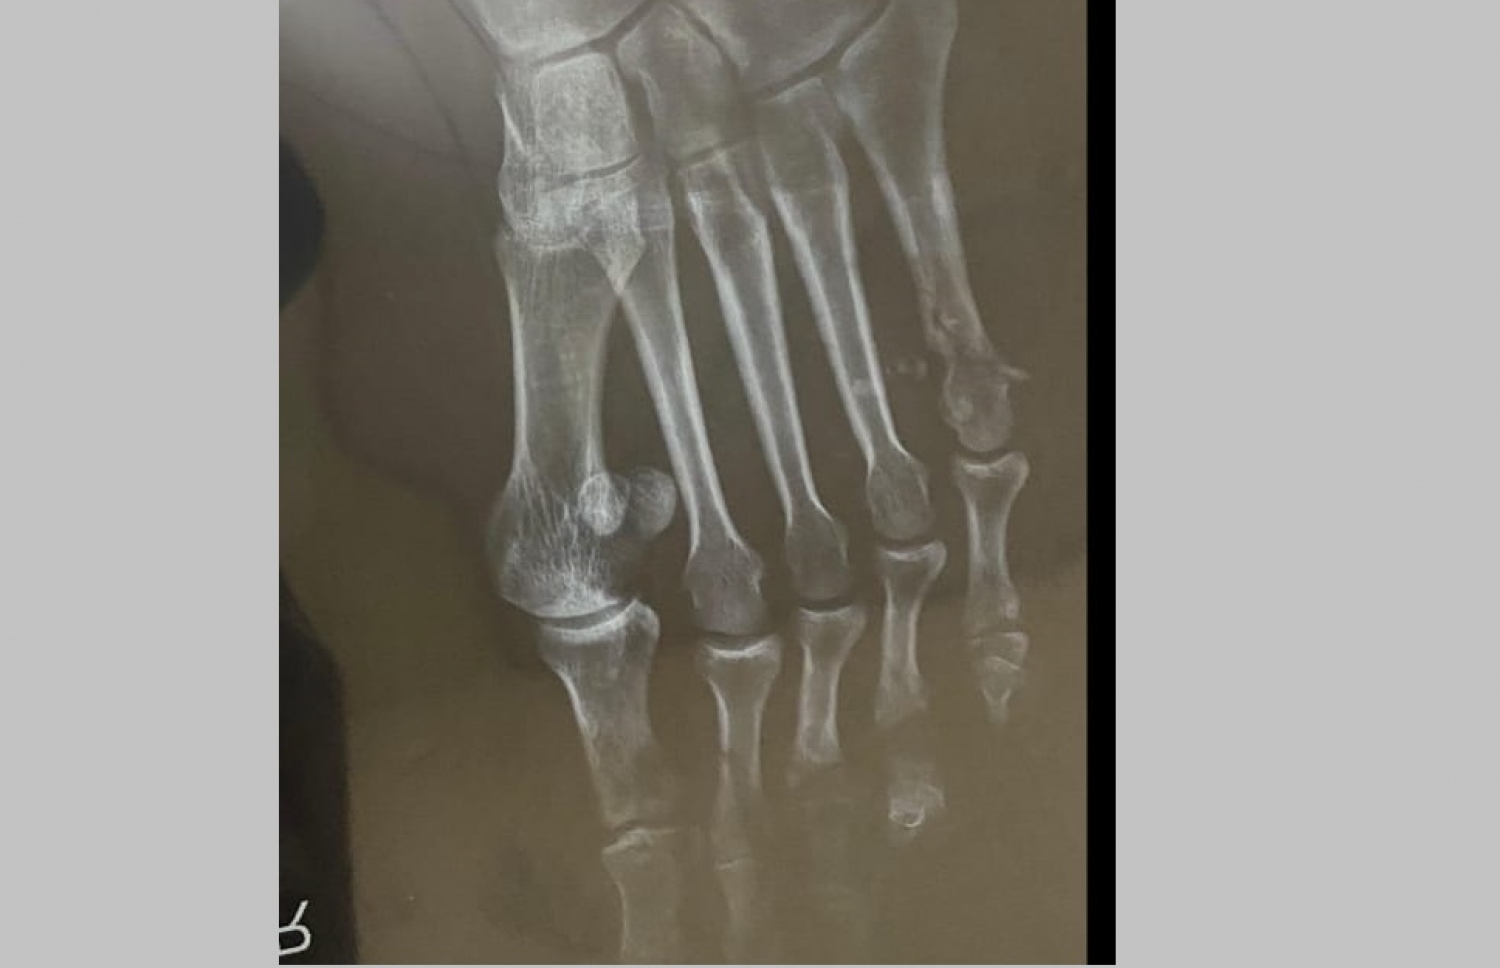

ހަމަލާގައި އާދަމްގެ ފަޔަށް ލިބުނު ގެއްލުން ފެންނަ އެކްސްރޭއެއް.

ބޮން ހަރުކޮށްފައި ހުރި ސައިކަލާ ވަރަށް ކައިރީގައި އާދަމް މަޑުކުރީ ވެސް އެ މަގުން ނަޝީދު ވަޑައިގަންނަވަންދެންނެވެ. އެހެން ހުއްޓައި އައިއީޑީ ގޮއްވާލުމުން އޭނާގެ ކަނާތު ފައިގެ ކުޑަވައި އިނގިލީގެ ކަށިގަނޑު ވަނީ ބިންދައިގެން ގޮސްފަ އެވެ. އެ ތަނުން ކުޑަކުޑަ ދަގަނޑުކޮޅެއް ނަގާފައިވެ އެވެ.